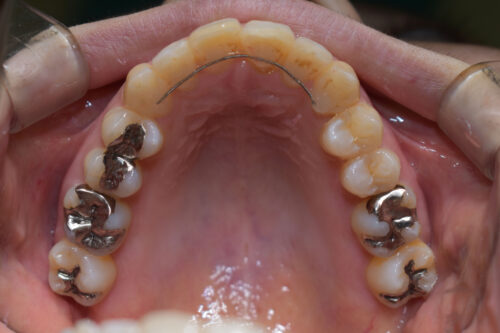

本症例も

上顎左右臼歯部に

歯科矯正用アンカースクリュー(デュアル・トップオートスクリュー)を用い

下あごを オートローテーションさせ

また 上下の歯列全体を

後方へ移動させることで

歯を抜かなくても

口元の改善も行いました。

上下の正中には 若干ずれが残存しましたが、

かみ合わせ重視で

終了いたしました。